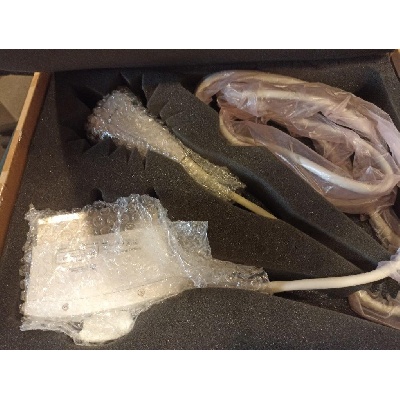

Használt 2D/ 3D / 4D ultrahang vizsgálófej

Használt 4-18 MHz-es lineáris vizsgálófej